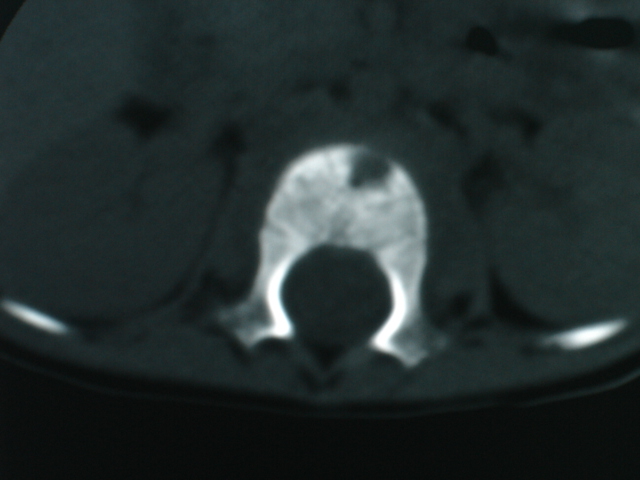

椎体周围见类软组织密度影,椎体见虫蚀样破坏,考虑tb.性。

椎体骨质破坏,椎体周围见软组织密度影.椎体结核

椎体破坏明显,周围软组织肿胀,椎间盘未见明显受累.结核

椎体结核合并冷脓肿形成。

椎体破坏明显,周围软组织肿胀,椎间盘未见明显受累.考虑椎体结核合并冷脓肿形成。

体破坏明显,周围软组织肿胀,椎间盘未见明显受累.考虑椎体结核合并冷脓肿形成.注意排除嗜酸性肉芽肿